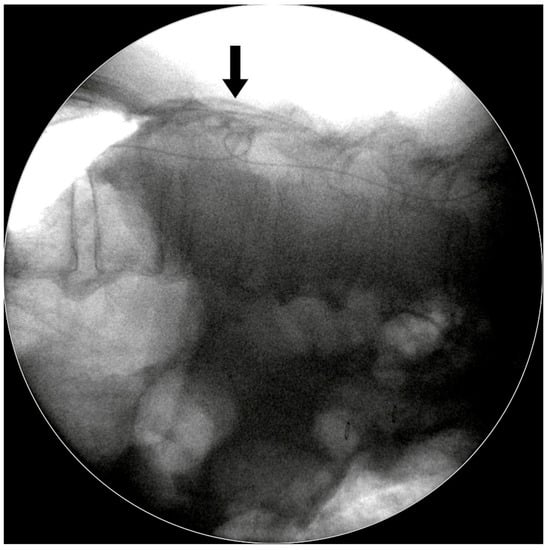

- It allowed us to easily perform lumbar tapping and insertion of the spinal catheter under fluoroscopic guidance. Sabah et al. revealed that insertion of an LP shunt without fluoroscopy guidance has a 15.8% chance of false positioning of the proximal end of the spinal catheter [11]. We designed the two-stage surgery with the patient in a prone then a supine position. In the first stage, the prone position simplified checking the true lateral view of the spine X-ray so that we could actually place the catheter in the correct position.

- It avoided the kinking of the lumbar spinal catheter in the thecal sac. In our experience, spinal catheter entanglement or twisting occurred in about 10%–15% cases, but we were able to correct it immediately under fluoroscopic guidance (Figure 5).